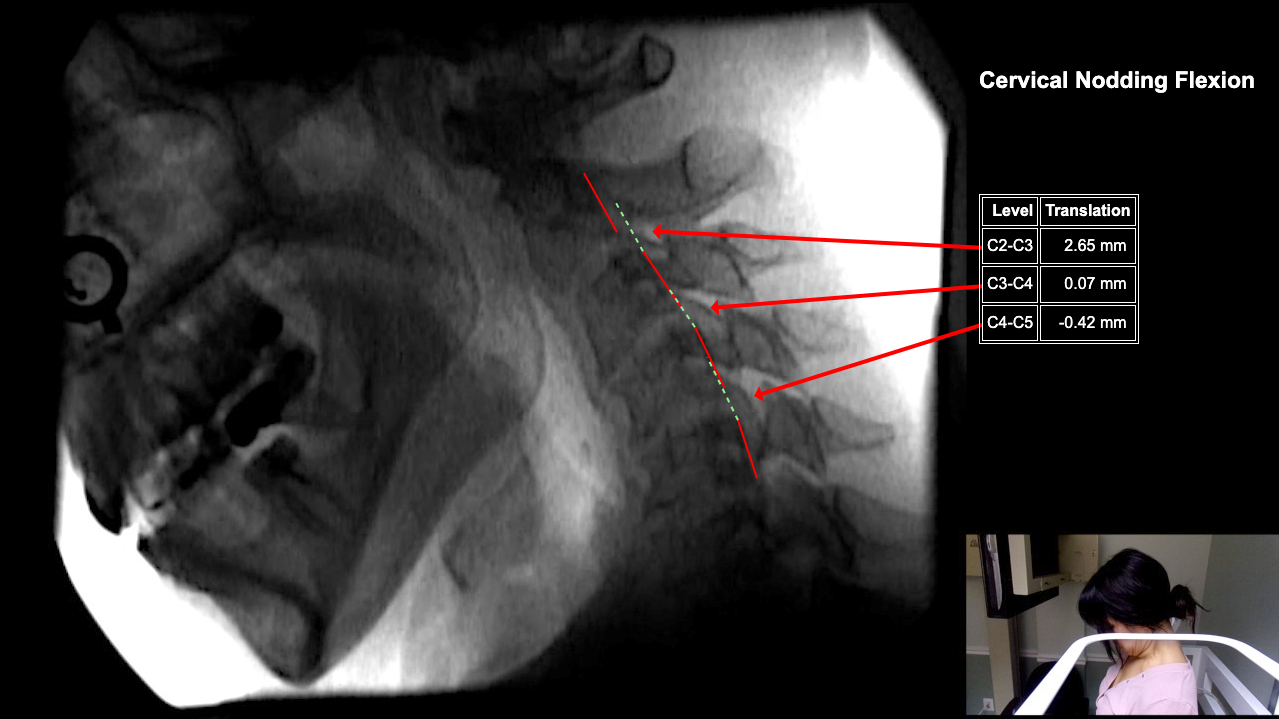

Image 2